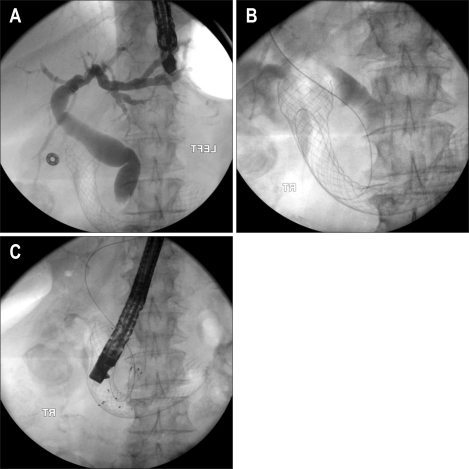

Fig. 6.

Successful combined endoscopic biliary and duodenal stent placement in type III duodenal stenosis. (A) The bile duct with a distal stricture is cannulated. (B) After placement of the biliary self-expandable metal stent (SEMS), the duodenal stricture is delineated with contrast agent. (C) The duodenal SEMS is deployed across the duodenal stricture with the proximal end just distal to the biliary SEMS.